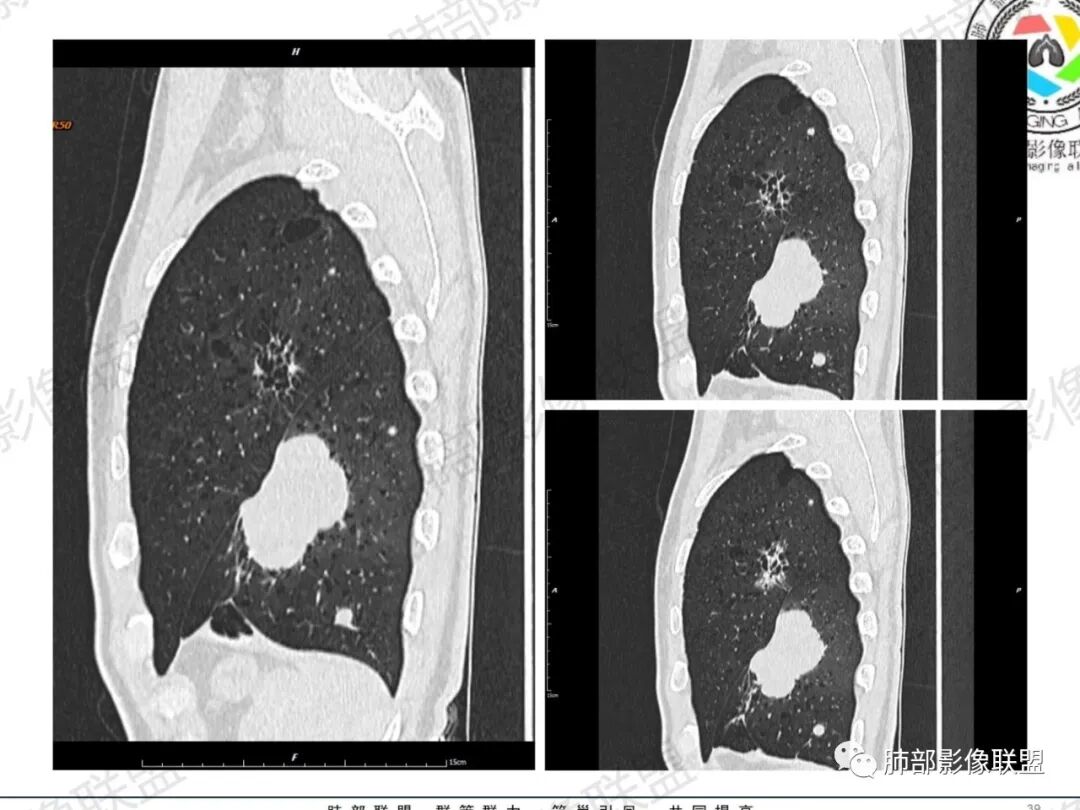

一切∮随缘:左肺下叶不规则肿块,边缘光滑,平直,局部彭隆,分叶,近端支气管堵塞,远端与胸膜相贴,平扫密度尚均匀,增强后不均匀强化,内部可见低密度坏死,胸膜下多发肺气肿,伴双肺散在光滑小结节,实验室肿瘤标志物高,考虑恶性:神经内分泌癌(大细胞),腺癌,鳞癌。

琦遇:恶性没有问题,肺气肿底子、病灶分叶、少许毛刺、叶间胸膜凹陷、部分边缘可见清晰的GGO、胸膜牵拉凹陷、局部胸水、近端支气管截断、部分支气管被推移、占位效应明显、强化特点为不均匀强化、内部有少许沼泽样低强化区,强化部分轻中强化为主、余肺可见转移性结节、左肺上叶似为囊腔型腺癌一枚,肿瘤标志物提示非小、神经内分泌,综合分析考虑大神泌、腺癌、腺鳞癌、鳞癌  同时左肺上叶囊腔型腺癌  肺转移

蕊:中老年男性,吸烟史,肺气肿背景,左肺上叶类圆形肿块影,边界清晰,边缘凹凸不平,有分叶,支气管进入阻断,临近胸膜栽赃,整体病灶膨隆,局部周围可以清晰ggo,临近叶间裂内凹,轻度强化,并可见多个低密度区,坏死可能,界线不清;肺内多结节,边缘光滑,考虑恶性伴转移,鳞癌、腺癌

傅昌瑜:中老年男性,肺气肿背景,右胸背疼痛1周。CEA、NSE、CYFRA—211升高。左上肺混合磨玻璃结节,内见较多空泡和扩张支气管。左下肺胸膜下肿块,边缘较光滑,深分叶,似有血管进入,与支气管关系不清,内见不均匀强化,见沼泽地样坏死,有胸膜栽赃。另两肺多发圆形小结节。考虑恶性并肺内转移,多原发可能性大,左上肺腺癌,左下肺病理难以判断,小细胞癌?鳞癌?

蓝天白云:中年男性,肺气肿背景,左肺下叶肿块,边缘膨隆,有分叶,内有湖泊样坏死,有轻中度强化,局部胸膜栽赃,收缩力不强,周围见肺气肿征象。左肺上叶混合磨玻璃影,边界清楚,考虑都是恶性,左上肺iac,左下肺腺鳞癌,或大细胞肺癌可能。两肺多发结节,考虑转移

LCNEC最常见的影像特征包括:(1)肿块发生部位:周围型肺癌为主,少数发生于肺中央。(2)肿块大小及形态。因肿瘤细胞生长迅速常形成较大肿块,因此其体积一般较大,直径常在3~10cm范围内,病灶常为不规则形软组织肿块。(3)肿块边界。多数学者报道大多数肿块边界清晰,边缘呈分叶状,毛刺征及“胸膜凹陷征”少见,认为与该病对周围组织浸润较轻及较少产生纤维瘢痕组织牵拉有关联。(4)肿块密度、强化特点及代谢情况。据文献报道,该类肿瘤因体积较大CT上常见软组织肿块,且多数密度不均匀,内见囊变坏死区,增强后呈轻或中度不均匀强化(可见强化者占75.7%),认为其强化特点与其内部肉眼可见坏死灶和肿瘤较大直径有关。(5)伴随症状及远处转移。该病恶性程度高,侵袭性强,常侵犯邻近结构,如胸膜、心包、邻近骨质或纵隔内组织等,易出现纵隔淋巴结转移,部分发生肺内及远处转移,少数早期可出现广泛远处转移。